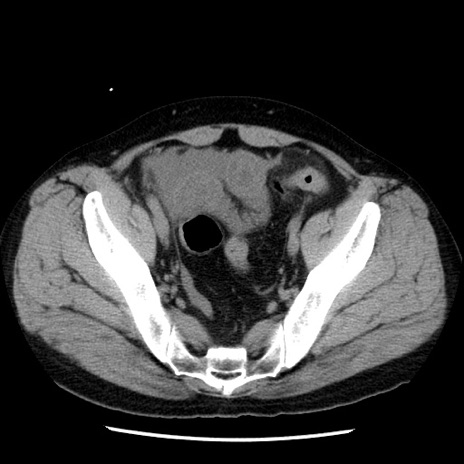

症例29(横断像)

【症例】40歳代男性

【現病歴】2日前から胃痛あり。徐々に周期的な激痛に変化した。本日になっても激痛があるため受診。

【身体所見】意識清明、BT 38-39℃台あり、腹部:膨満、やや硬、右下腹部に圧痛あり。

【データ】WBC 8500、CRP 23.26